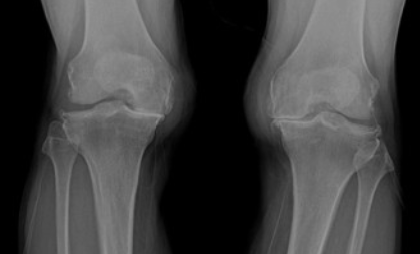

2.퇴행성 관절염의 증상

- 관절을 움직일 때 통증이 있습니다.

- 아침에 일어나면 관절이 뻣뻣하게 느껴집니다.

- 관절에서 "뚝뚝" 소리가 납니다.

- 관절이 붓고 염증이 생길 수 있습니다.

- 관절이 제대로 움직이지 않아서 생활이 불편해집니다.